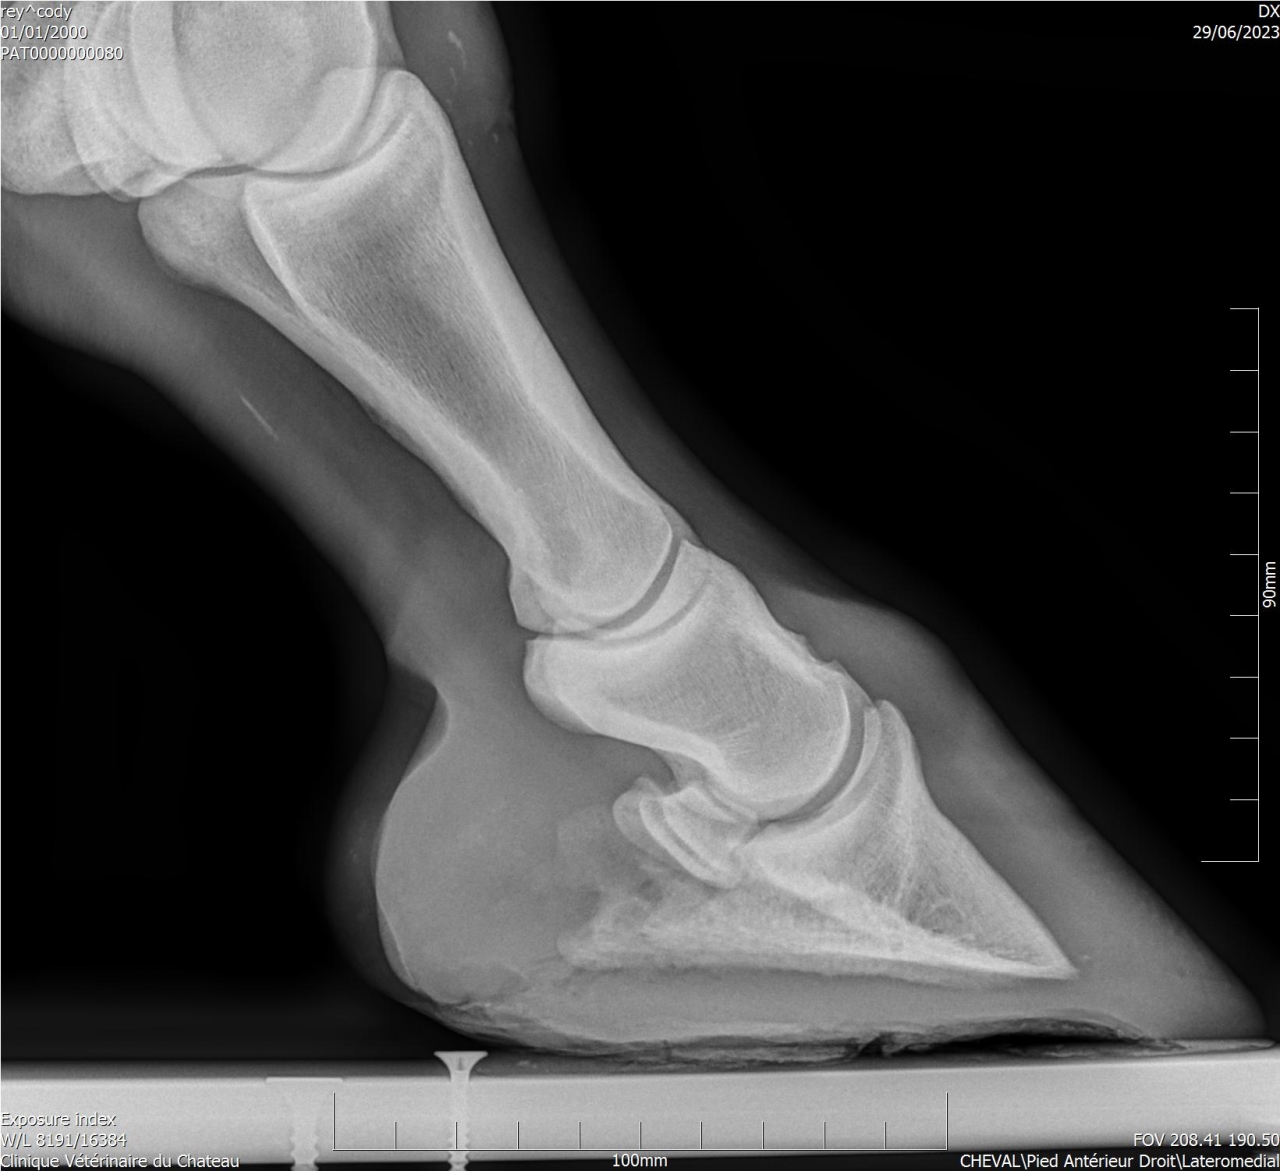

| Dire merci | Cody a une sensibilité que personne n'arrive à expliquer ... Les radios montrent une ossification des processus palmaires sur les 2 antérieurs, et une légère bascule de P3 sur l'antérieur gauche. A priori le naviculaire est correct. J'ai trouvé un maréchal-ferrant qui pose des Duplos. Vaut il mieux brocher ou coller ? |

| Dire merci | Deux personnes m'ont parlé des Duplo, les vétos ont conseillé ferrure en M ou ferrure normale ... L'année dernière Cody a été ferré avec des fers oignons et plaques en cuir, ça n'a rien changé. Ces fers ont été conseillés par le maréchal-ferrant car le véto consulté à l'époque conseillait des egg bar. Il me semble qu'avec l'ossification des processus palmaires les fers en métal n'étaient pas l'idéal. Voici les radios : ![]() ![]() ![]() ![]() J'essaye de régler les problèmes physiques pour voir si ça change quelque chose monté. Je commence par les pieds. |